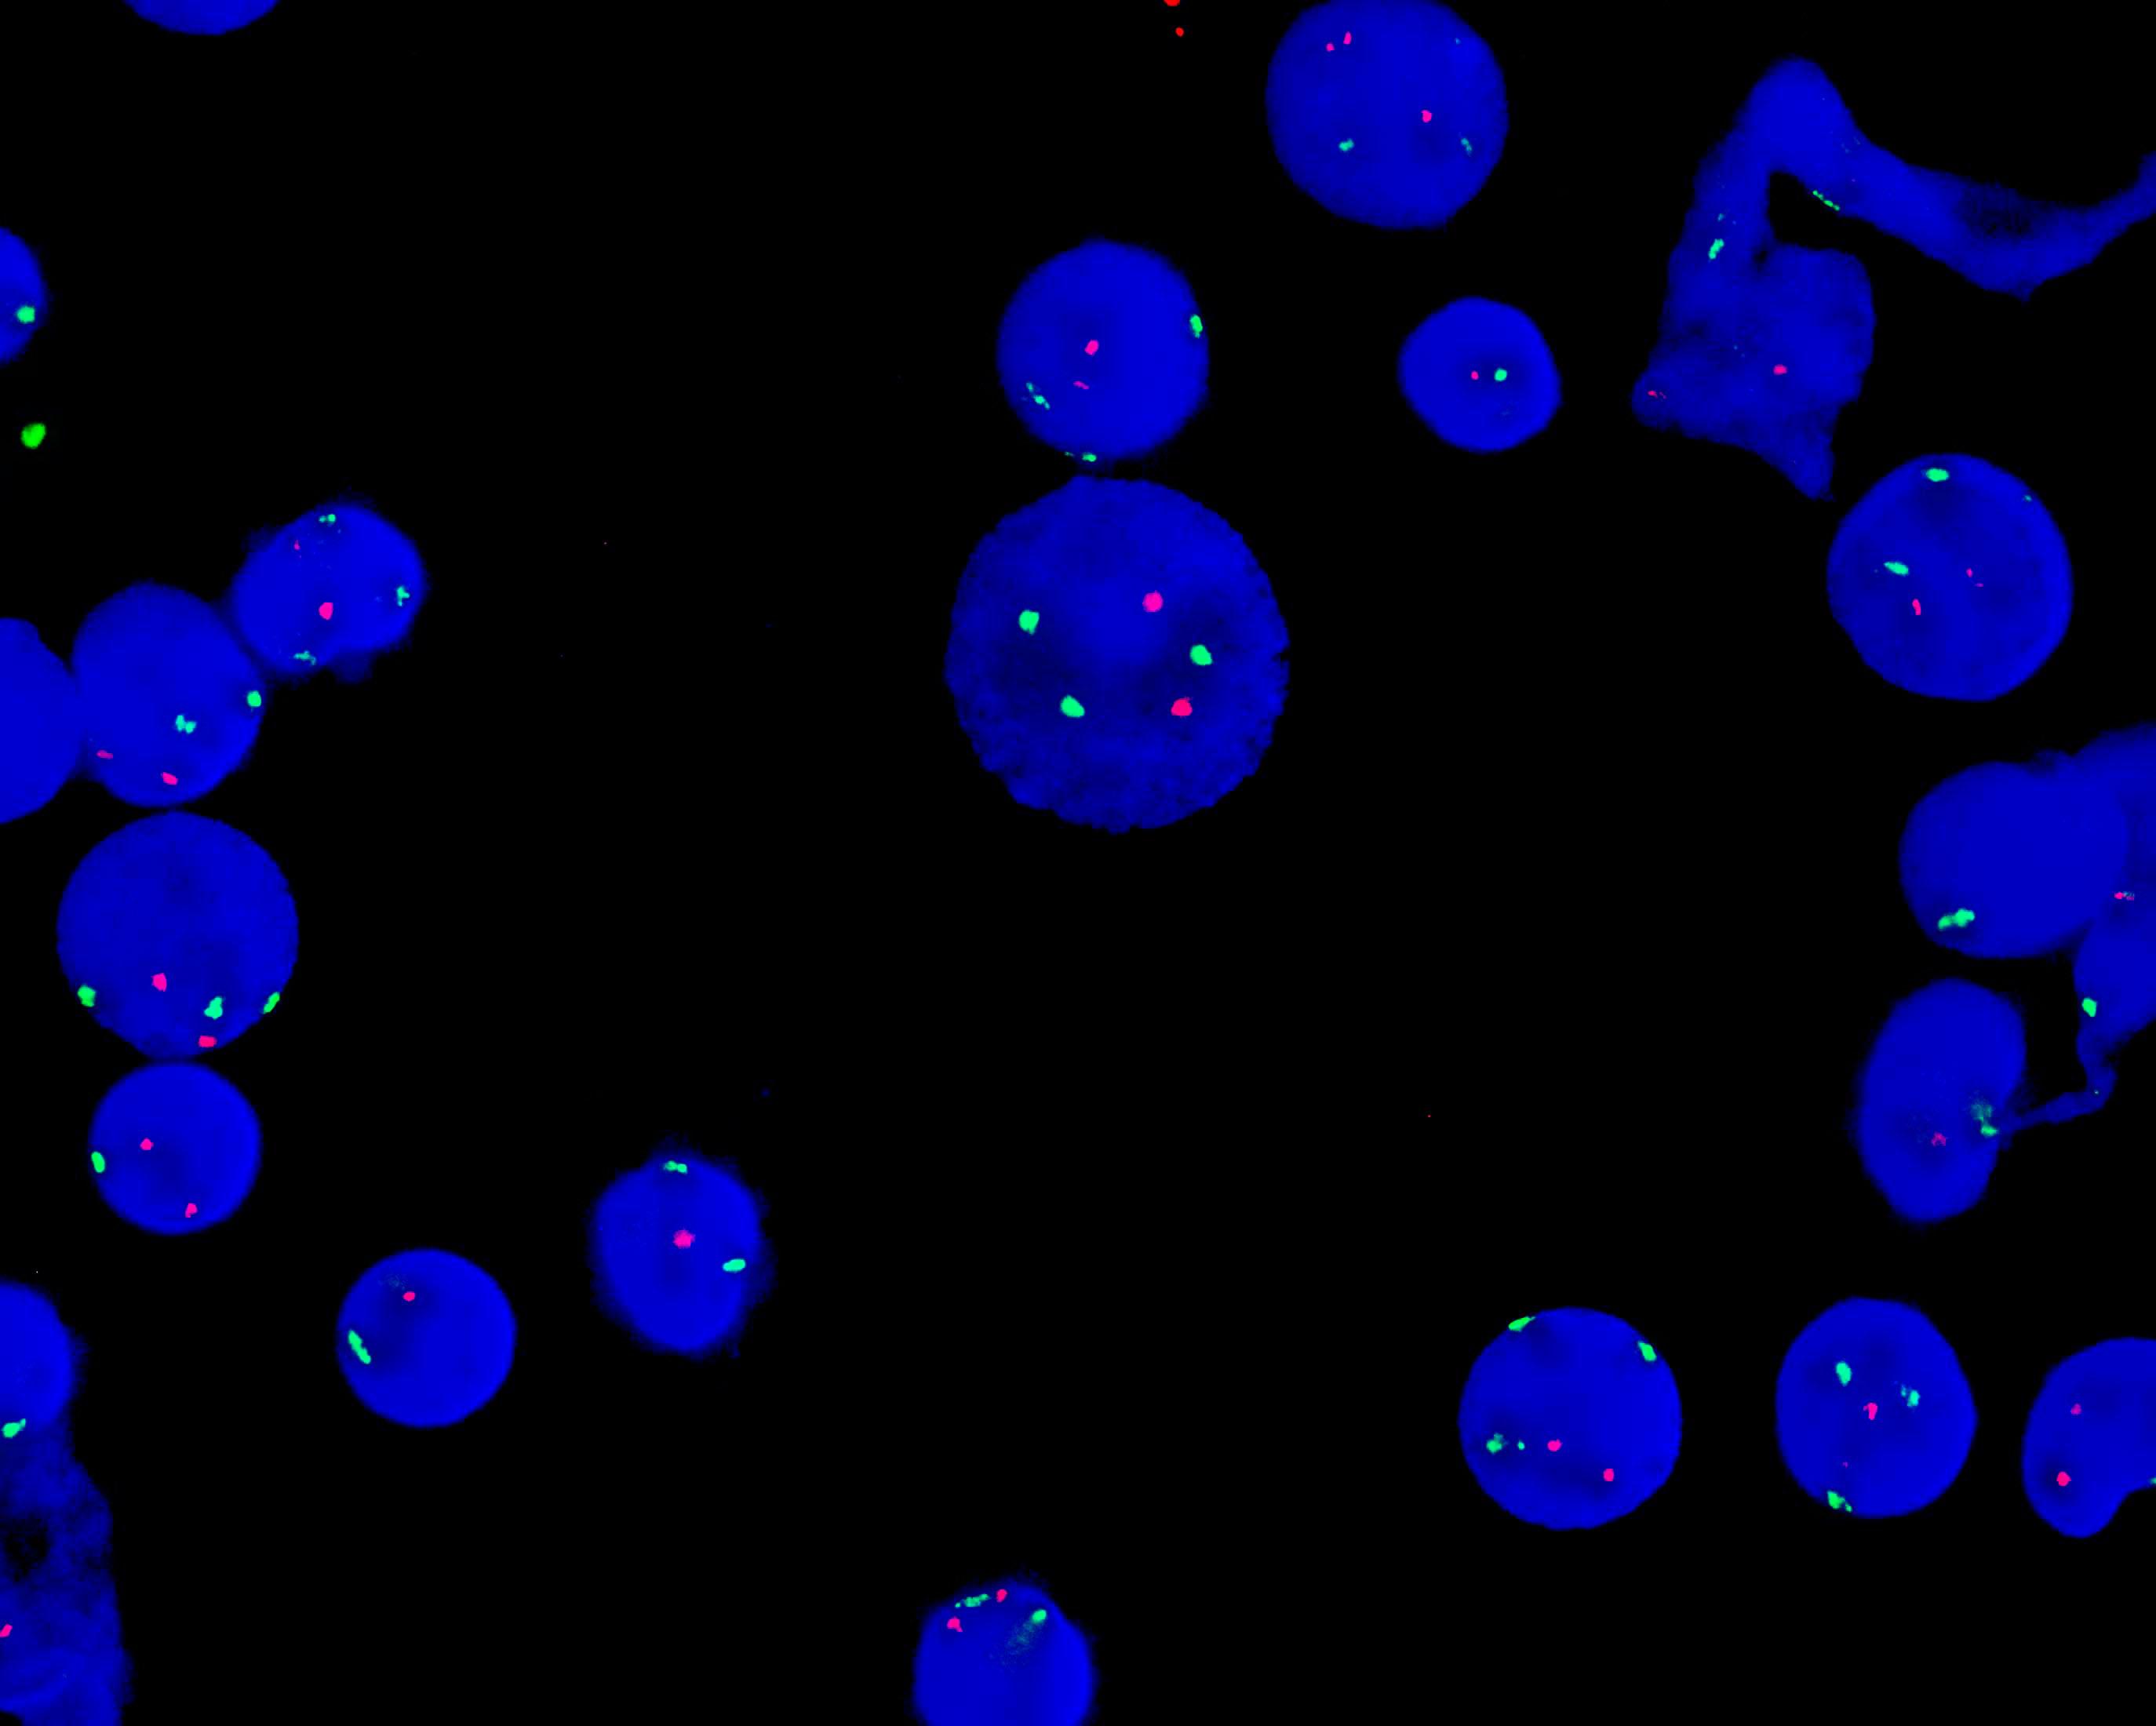

D20S108/CEP8 dual color probe

D20S108 gene locus (20q12) labeled as orange, with a length of 320 kb. 8 chromosome centromere (CEP8) labeled as green.